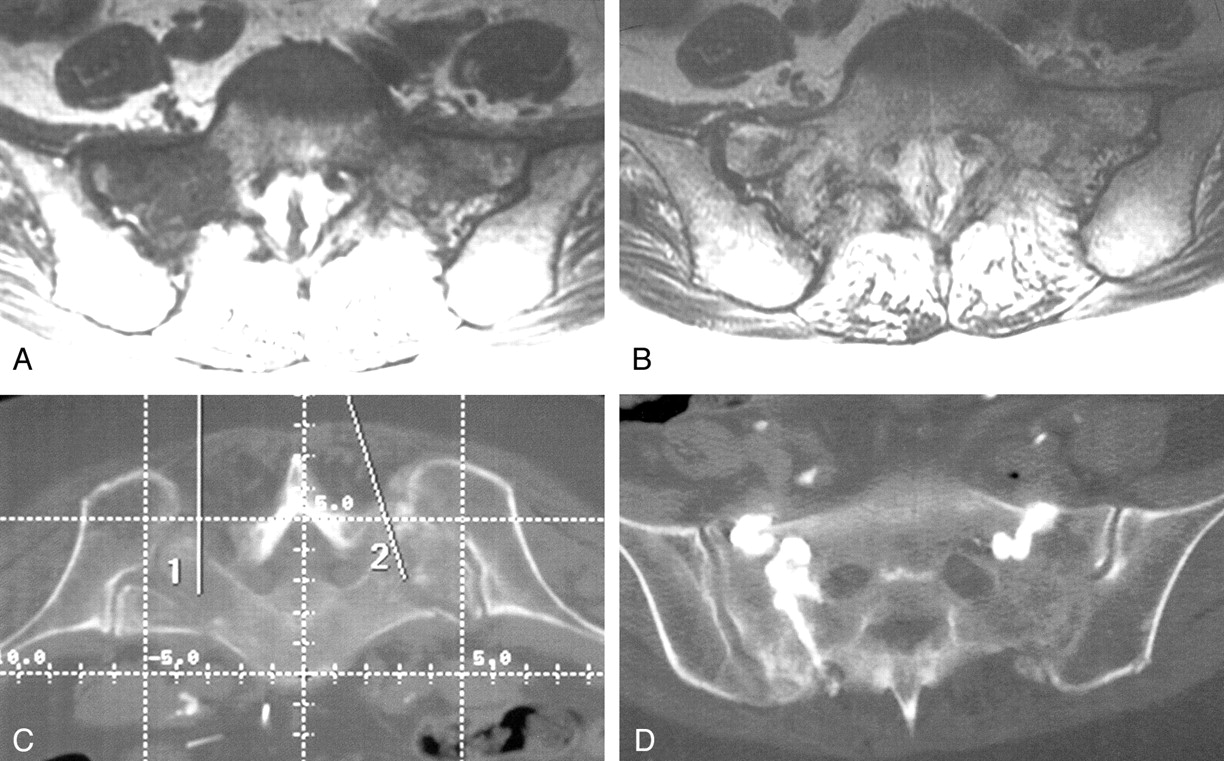

A 76-year-old woman was referred for vertebroplasty for intermittent chronic lower back pain recently aggravated by a fall. The severity of her pain necessitated a wheelchair for mobility. During examination, she reported tenderness over L4, but her severe sacral pain dominated her presentation. Although a pelvic radiograph (Fig 1A) was normal, bone scintigraphy (Fig 1B) revealed the classic H sign of a sacral insufficiency fracture in addition to an active L4 compression fracture. As a planning step, preoperative pelvic CT showed sclerotic changes with cortical disruption bilaterally, confirming the sacral insufficiency fractures (Fig 1C). In addition to L4 vertebroplasty, she consented to attempt the sacroplasty alternative.

Case 1, a 76-year-old woman with low back pain.

A, Pelvic radiograph shows degenerative lumbar changes. Note, however, that the sacrum is unremarkable.

B, Bone scan shows the H sign diagnostic of a sacral insufficiency fracture. Prominent renal activity on the scan is a normal finding.

C, Cortical disruption (arrows) on a non-contrast-enhanced pelvic CT scan confirms fracture.

D and E, Anteroposterior (D) and lateral (E) fluoroscopic images show cement in the L4 vertebral body and cement bilaterally in the sacral ala. The lateral view illustrates the difficulty with visualization within the sacrum during this technique.

F, Postoperative pelvic CT scan shows cement within the bilateral superior sacral ala in the vicinity of the fracture lines

G, Follow-up pelvic radiograph shows the cement within the superior sacrum

After L4 vertebroplasty with standard prone positioning under conscious sedation with fentanyl and midazolam, the fluoroscopy unit was placed obliquely to provide access parallel to the sacroiliac joint. Biplane fluoroscopy was used to guide the needle into the sacrum, although the lateral view was limited in its usefulness for position confirmation. Using the Parallax injection system (Ezflow Cement Delivery System, Parallax Medical Inc., Scotts Valley, CA), we injected the polymethylmethacrylate cement and barium powder mixture under fluoroscopic monitoring (Fig 1D and E). The overlapping bony pelvis obscured sacral visualization, complicating our assessment of whether the injected cement was contained within the sacrum. A postoperative pelvic CT scan showed cement within the bilateral superior sacral ala, in the vicinity of the fracture lines (Fig 1F). Postoperative instructions included remaining in a supine position for 4 hours, with discharge home afterward.

Pain relief was immediately evident that night, with virtually complete relief of symptoms. At a 1-month follow-up clinical visit, she remained pain free, had regained her independence from a wheelchair and walker, and no longer needed analgesic medication. A follow-up pelvic radiograph showed the cement within the superior sacrum (Fig 1G). By telephone report 16 weeks after the procedure, the patient continued to be pain free with no recurrence of lower back complaints despite two minor falls at home in the interim.